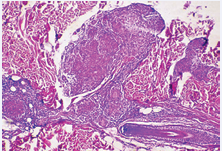

Microbiological examination of the skin substrata in direct microscopy had not confirmed the presence of M.Tuberculosis. The biopsy of an erythematosquamous lesion of the left arm was taken which revealed granulomatous structures, consisting of epitheloid histiocytes and polynucleid grant cells, surrounded by small lymphocytes. No central necrosis or caseiting was seen (Figure 4).

Figure 4 Granulomatous structures without central necrosis.